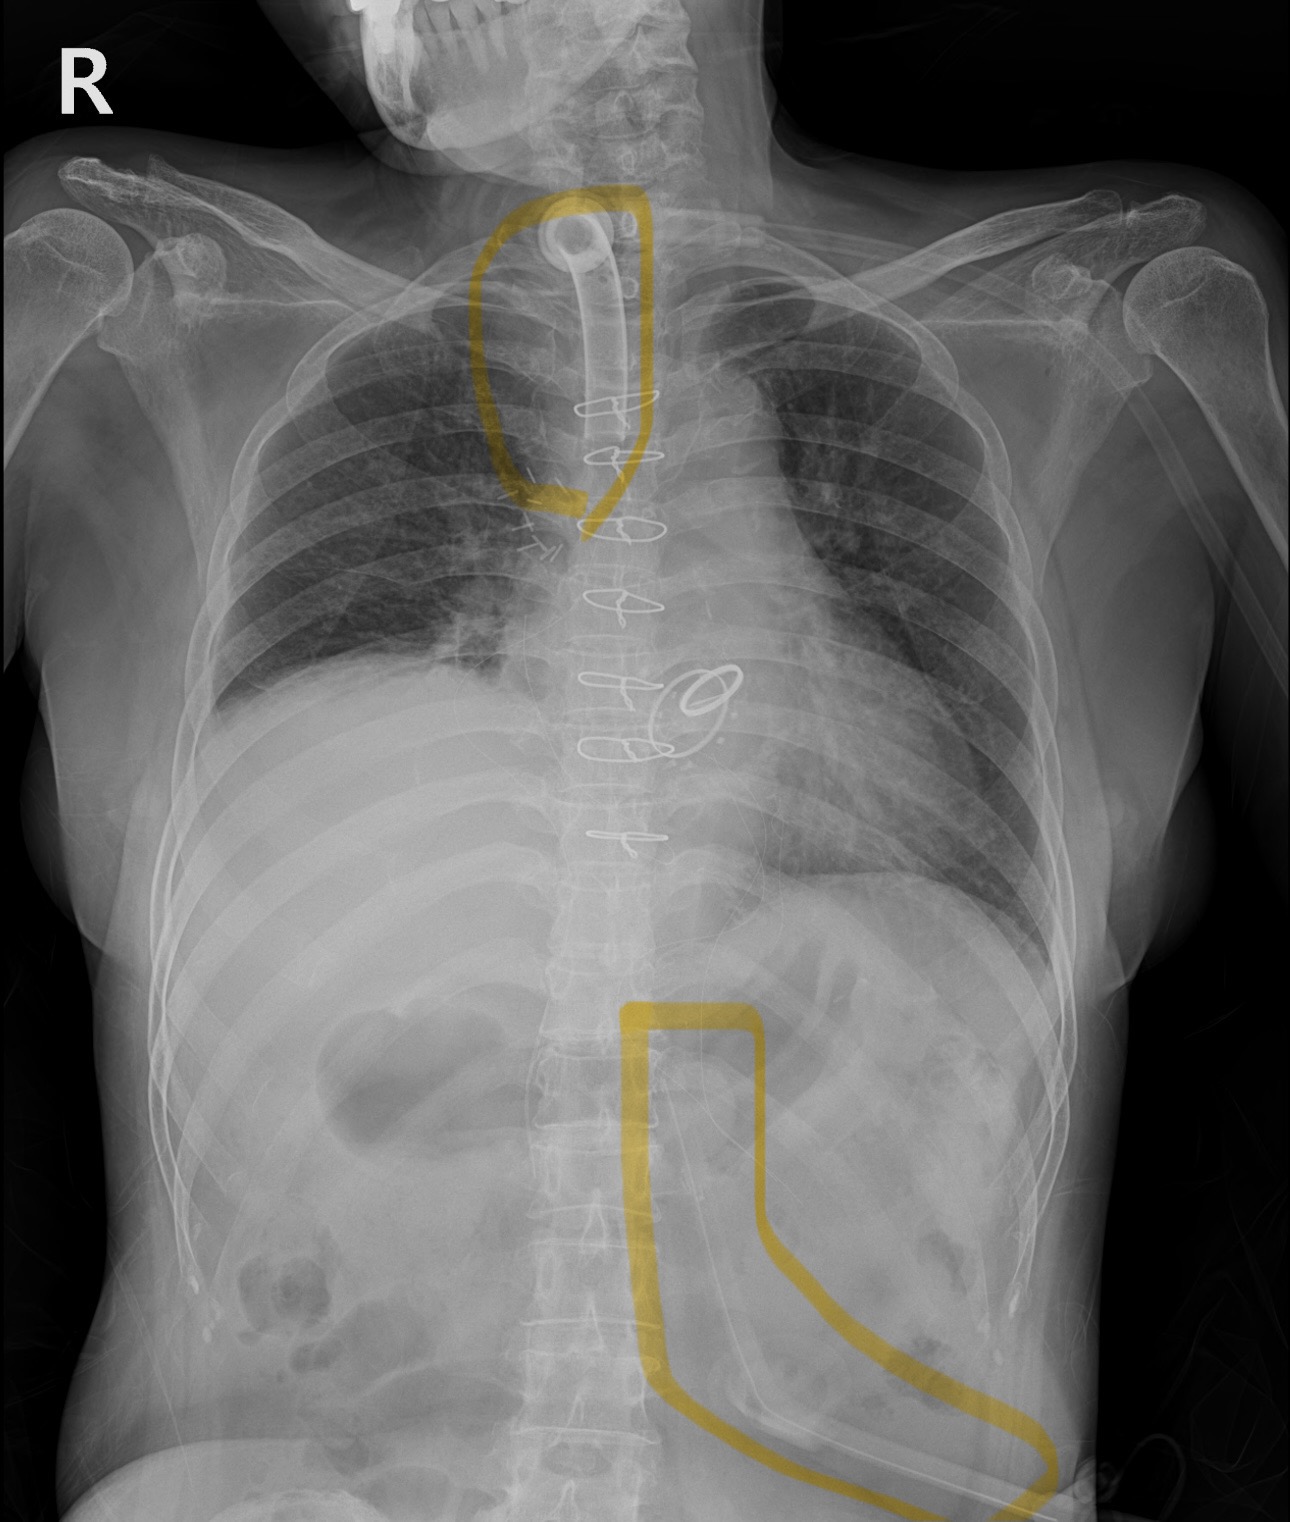

66세 여성분으로 과거 대동맥판막 및 삼천판막 치환수술을 받았고, 판막기능 문제로 인한 ARDS(급성호흡곤란증후군)이 발생하여 입원 했다가 중환자실에서 1달정도를 계셨던 분이다.

오랜 기계호흡으로 기관절개술 및 경피적위루술까지 진행했던 분으로

위쪽 노란색 표시가 기관절개후 유지하는 tracheal tube, 아래 복부쪽 노란색 표시가 PEG tube(경피적 위루술 튜브)

최근 x ray에선 모두 제거된 상태이다!